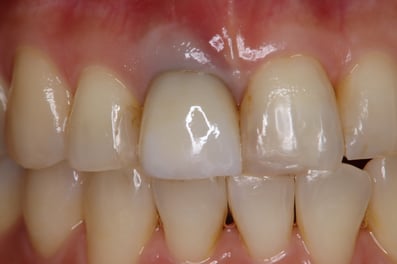

抜歯した直後にインプラントを埋入し、仮の歯を作製、唇側の骨のボリュームを保つために人工骨と結合組織を同時に移植する非常に優れた方法です。

Simplified Microscopic Implant surgical Lifelike Esthetics を略した手術名で、米国カルフォルニア州サンタバーバラで歯周病専門医として開業されていた、 Dr. Dennis Shanelec(故人)が考案した治療法です。抜歯した直後に仮歯を入れることによって,歯を取り巻く骨(硬組織)や歯肉(軟組織)の状態を維持できる非常に優れた方法です。しかし、手術としての難易度は非常に高いレベルに位置づけられます。